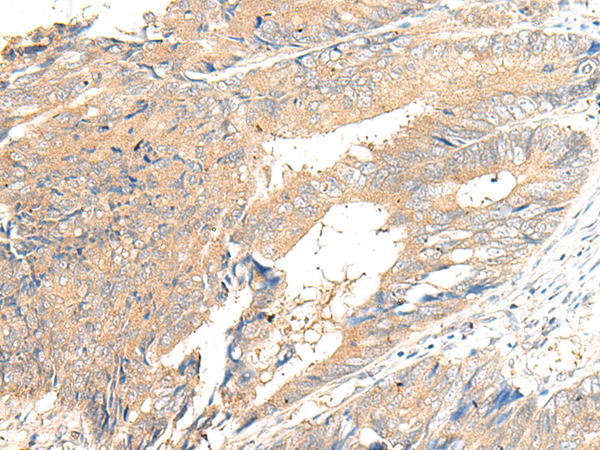

The image is immunohistochemistry of paraffin-embedded Human cervical cancer tissue using 47590(GPR132 Antibody) at dilution 1/20.(Original magnification: 200)

The image is immunohistochemistry of paraffin-embedded Human colorectal cancer tissue using 47590(GPR132 Antibody) at dilution 1/20.(Original magnification: 200)